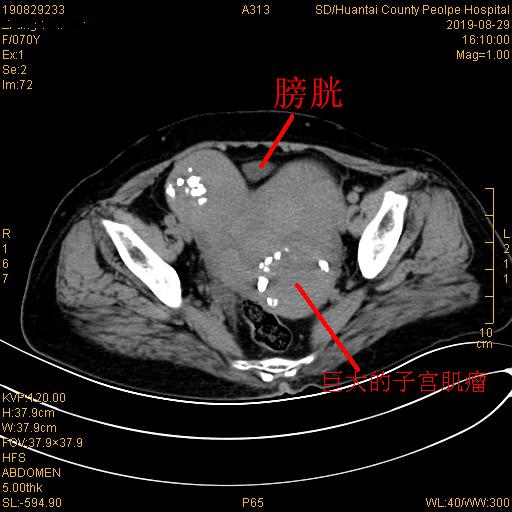

本以为是普通的输尿管结石碎石手术,可患者的CT片让在场医生和患者家属都大吃一惊。患者体内有一个直径约13cm的巨大子宫肌瘤,原本膀胱的位置被肌瘤完全占据,膀胱被挤到了盆腔的一角,这种情况下输尿管的开口非常难找。